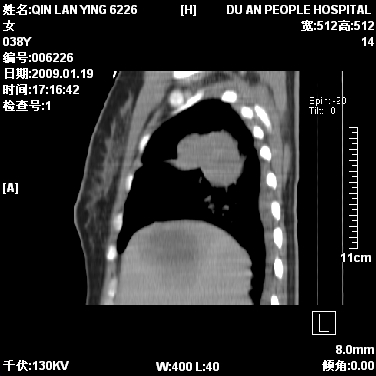

女,38岁,胸疼1个月。wbc:1万4

1)右肺中央型肺癌并右肺上叶阻塞性肺炎、节段性肺不张,纵隔淋巴结转移、右侧胸膜转移、肝脏转移。2)右侧胸腔少量积液。

本病例有几个容易诊断的地方:1、右肺上叶前段支气管闭塞,肺不张。2、淋巴结明显肿大。3、肝脏多个类圆形低密度影呈“牛眼征”改变,高度提示转移。

从影像学角度分析      右肺上叶中央型肺癌,并阻塞性不张、肺炎,纵隔淋巴结、膈顶淋巴结转移。

肝内两个大小不等低密度结节,内可见更低密度影,首先考虑肝内转移瘤,但联想到患者wbc1万4,建议楼主还是做个增强比较明确,除外肝脓肿的可能。